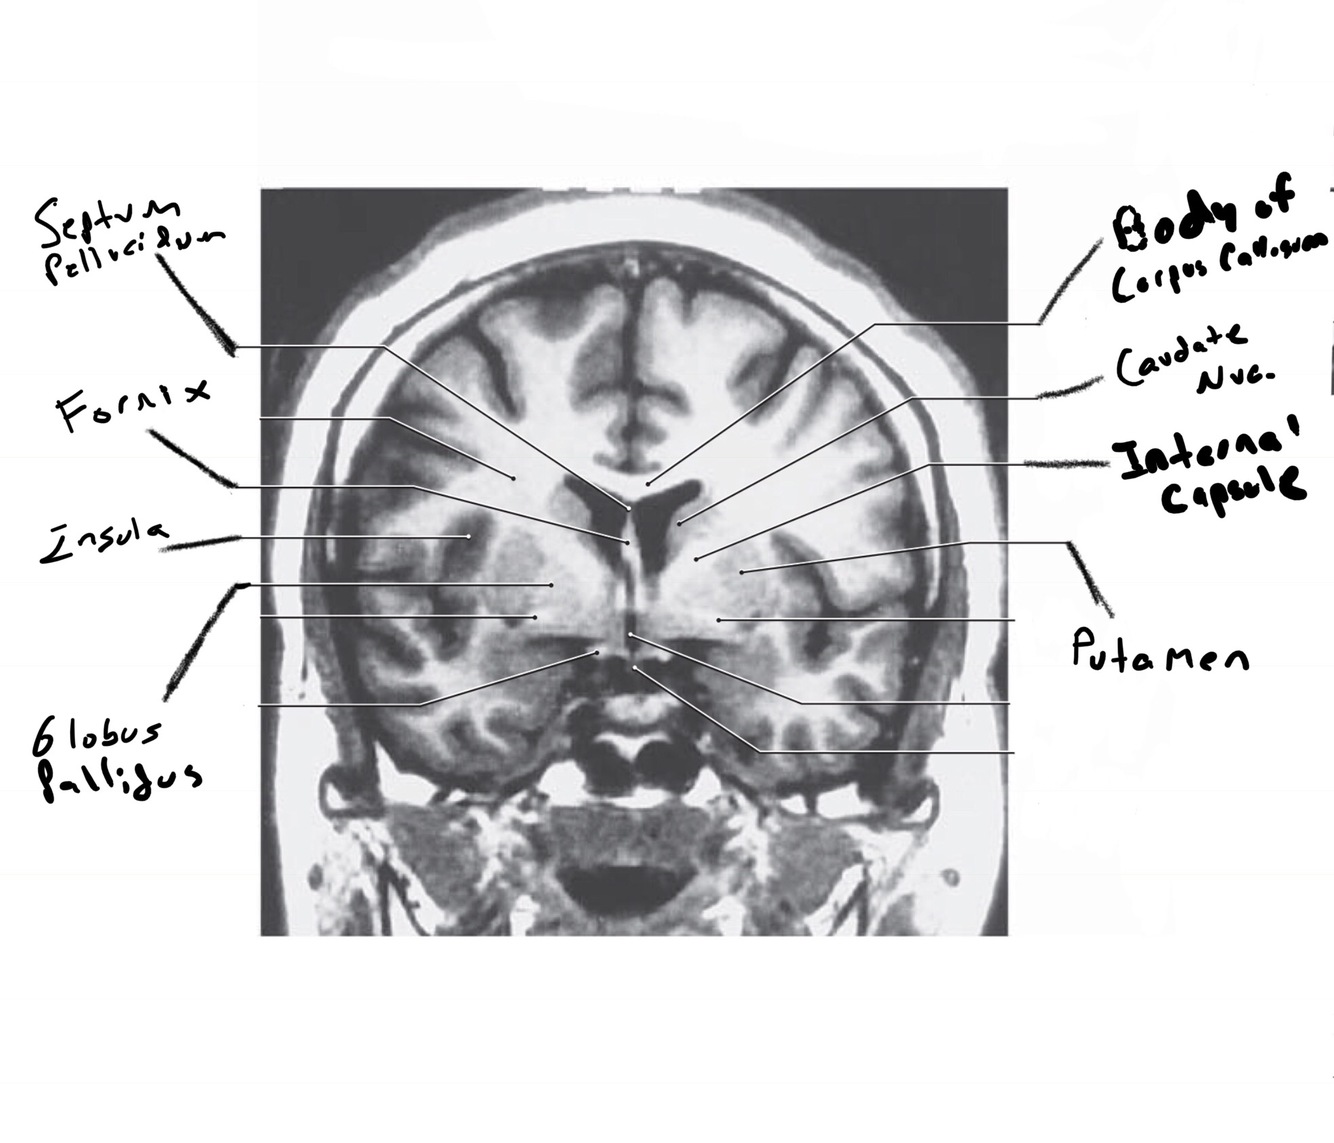

The structure indicated by the red line is?